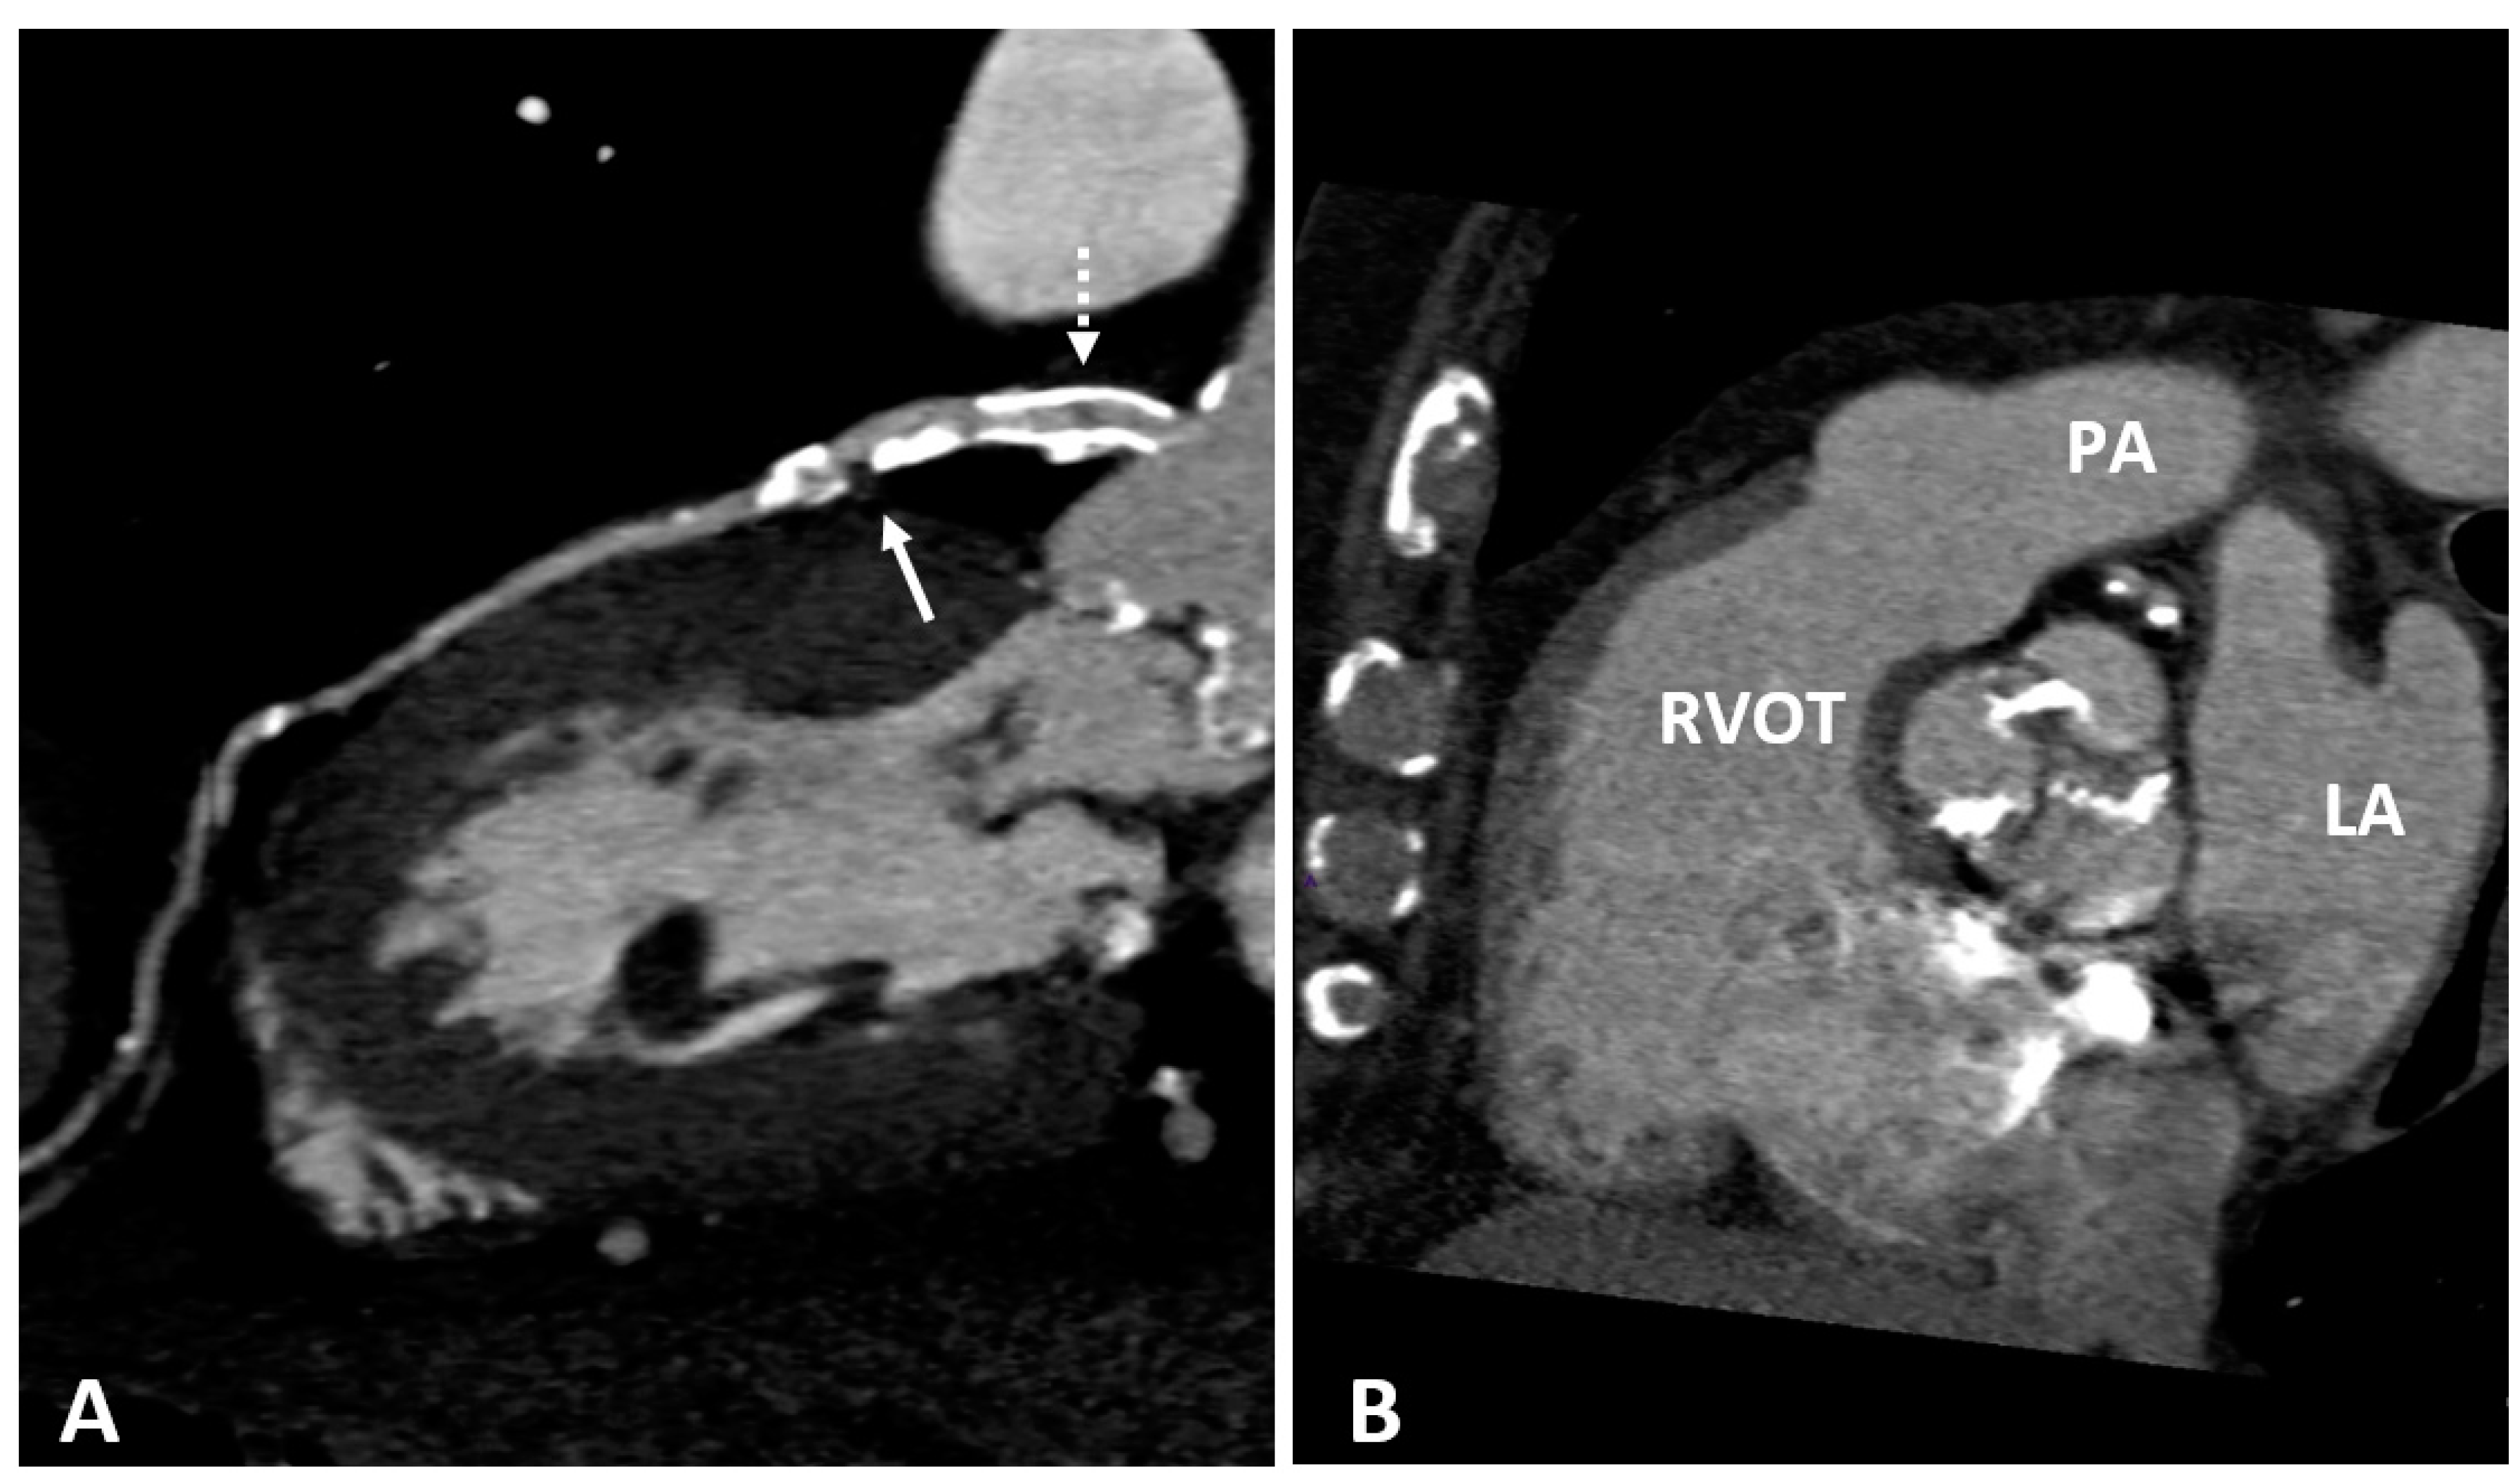

The intravenous administration of iodine contrast media allows the assessment of coronary stenosis and several adverse coronary plaque characteristics, such as spotty calcification, positive remodeling, and low-attenuation non-calcified plaques which identify a large necrotic core [68,69]. (Figure 2 and Figure 3). However, smaller components such as microcalcifications and TCFA cannot be detected because their dimension is ten times lower than the spatial resolution of CTCA (about 500 microns) [70].

Figure 3.

(A) CTCA showing the left main (LM) and left anterior descending (LAD) coronary arteries of a patient who underwent coronary angioplasty (PTCA) and stent positioning in the LM. A non-calcified low density soft plaque (white arrow) is shown between calcific plaques; the hypodense spot (dashed white arrow) within the stent may indicate initial intrastent restenosis. Calcification of the aortic valve leaflets. (B) CTCA of the same patient reformatted in the plane of the aortic valve shows calcification of the aortic leaflets. RVOT: right ventricle outflow tract; LA: left atrium; PA: pulmonary artery.